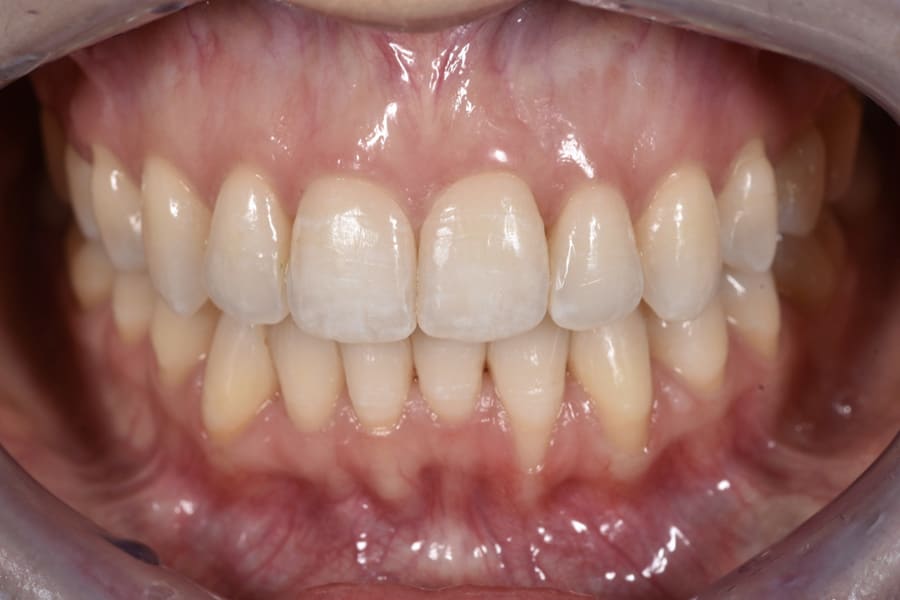

A 31-year-old female patient presented with the following intraoral conditions: an anterior open bite, bimaxillary crowding, negative crown torque, early “black triangles,” and a thin phenotype/biotype with early recessions. Her extraoral situation included a gummy smile with high-lip mobility, asymmetric arch forms and posterior corridors, and incompetent lip closure (Figure 2 through Figure 4). Collectively, these factors increase esthetic and periodontal risk and favor posterior intrusion over anterior intrusion.4-8,12-16